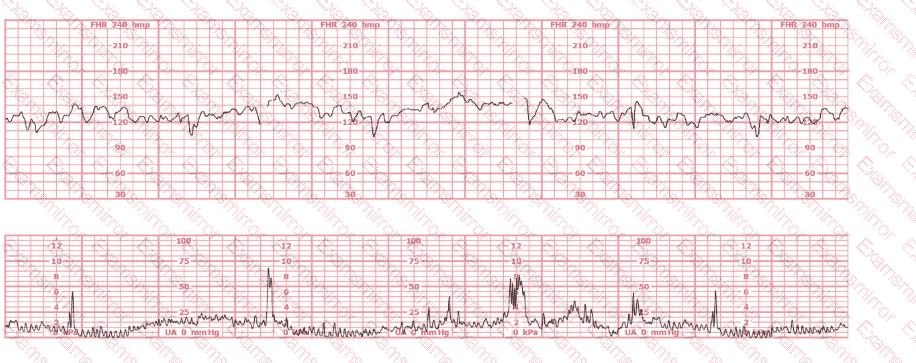

A woman (G1P0) arrives in triage with a pain score of 4/10 at 39-weeks gestation. The fetal heart rate tracing shown is obtained. The best intervention is to: